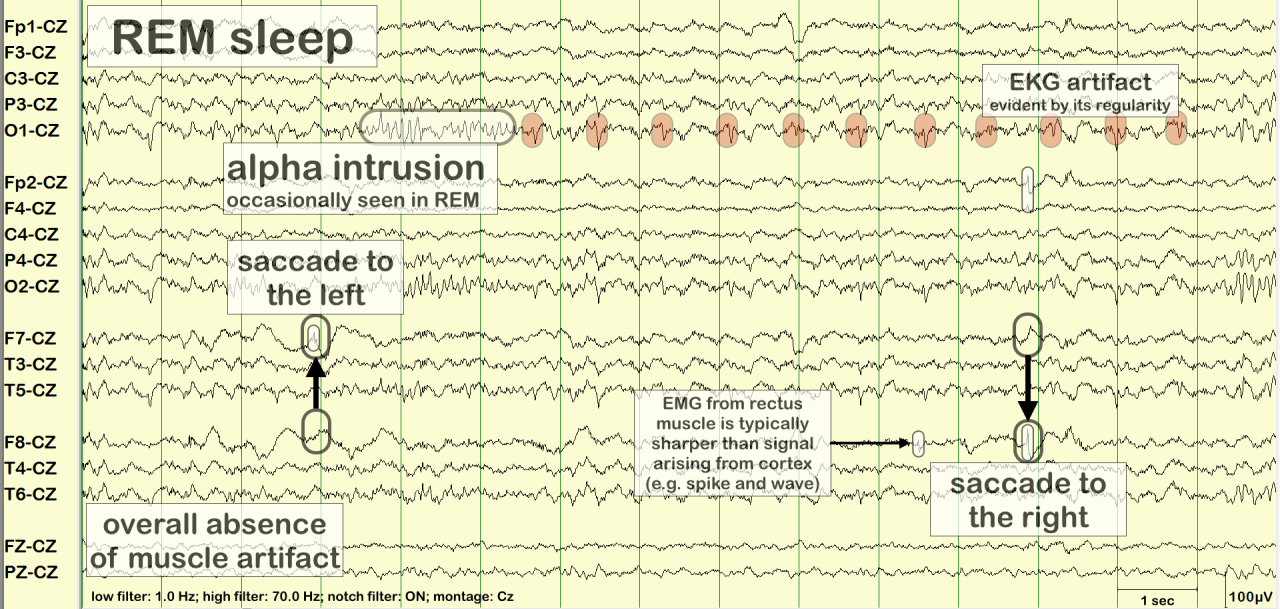

REM (Rapid Eye Movement) sleep is a crucial phase of the sleep cycle, characterized by rapid movements of the eyes, increased brain activity, and vivid dreaming. It accounts for approximately 20-25% of an adult’s sleep time and plays a vital role in cognitive functions such as memory consolidation, emotional regulation, and creativity. Understanding the physiological processes that occur during REM sleep can enhance our appreciation of its importance.

During REM sleep, several physiological changes take place. The brain exhibits heightened activity akin to wakefulness, which can be observed through brain wave patterns. This phase is marked by increased heart rate, irregular breathing, and the temporary paralysis of major muscle groups, preventing the sleeper from acting out dreams. The body experiences a drop in core temperature and changes in hormonal levels, including surges in neurotransmitters like acetylcholine, which promote dreaming. REM sleep typically occurs after about 90 minutes of sleep and recurs multiple times throughout the night, lasting longer with each successive cycle.

In contrast, REM sleep is marked by increased brain activity, rapid eye movements, and vivid dreaming. This stage is essential for cognitive functions such as memory consolidation, problem-solving, and emotional regulation, which differentiates it significantly from the restorative processes occurring during non-REM sleep stages.

Recent advancements in neuroimaging techniques, such as functional MRI (fMRI) and polysomnography, have transformed REM sleep studies. These methods allow for the real-time observation of brain activity during different sleep stages, revealing vital information about the neural mechanisms underlying REM sleep. Additionally, wearable technology has become a valuable asset, providing data on sleep patterns and quality in naturalistic settings.